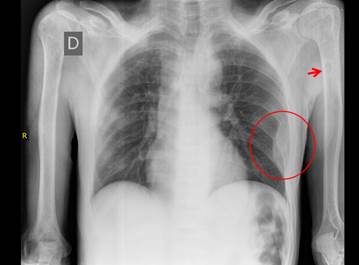

La radiografía de tórax (figura 1) mostró lesión expansiva en porción media de arco de 6° y 7° costillas izquierdas, sin lesiones parenquimales. Incidentalmente se observó una lesión quística en tercio distal de diáfisis humeral izquierda, la misma que se aprecia mejor en ventana mediastínica de una TEM de tórax (figura 2).